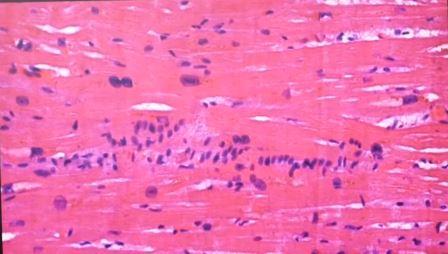

Caso severo, linfocitos en pared vascular

Infarto pulmonar que no debería ser mortal, se ven los linfocitos

Vaso con infiltración de linfocitos

VASCULITIS Y PERIVASCULITIS

Linfocitos, “¿qué están haciendo en la aorta? ¡por Dios!”, dice sorprendido el experimentado patólogo.